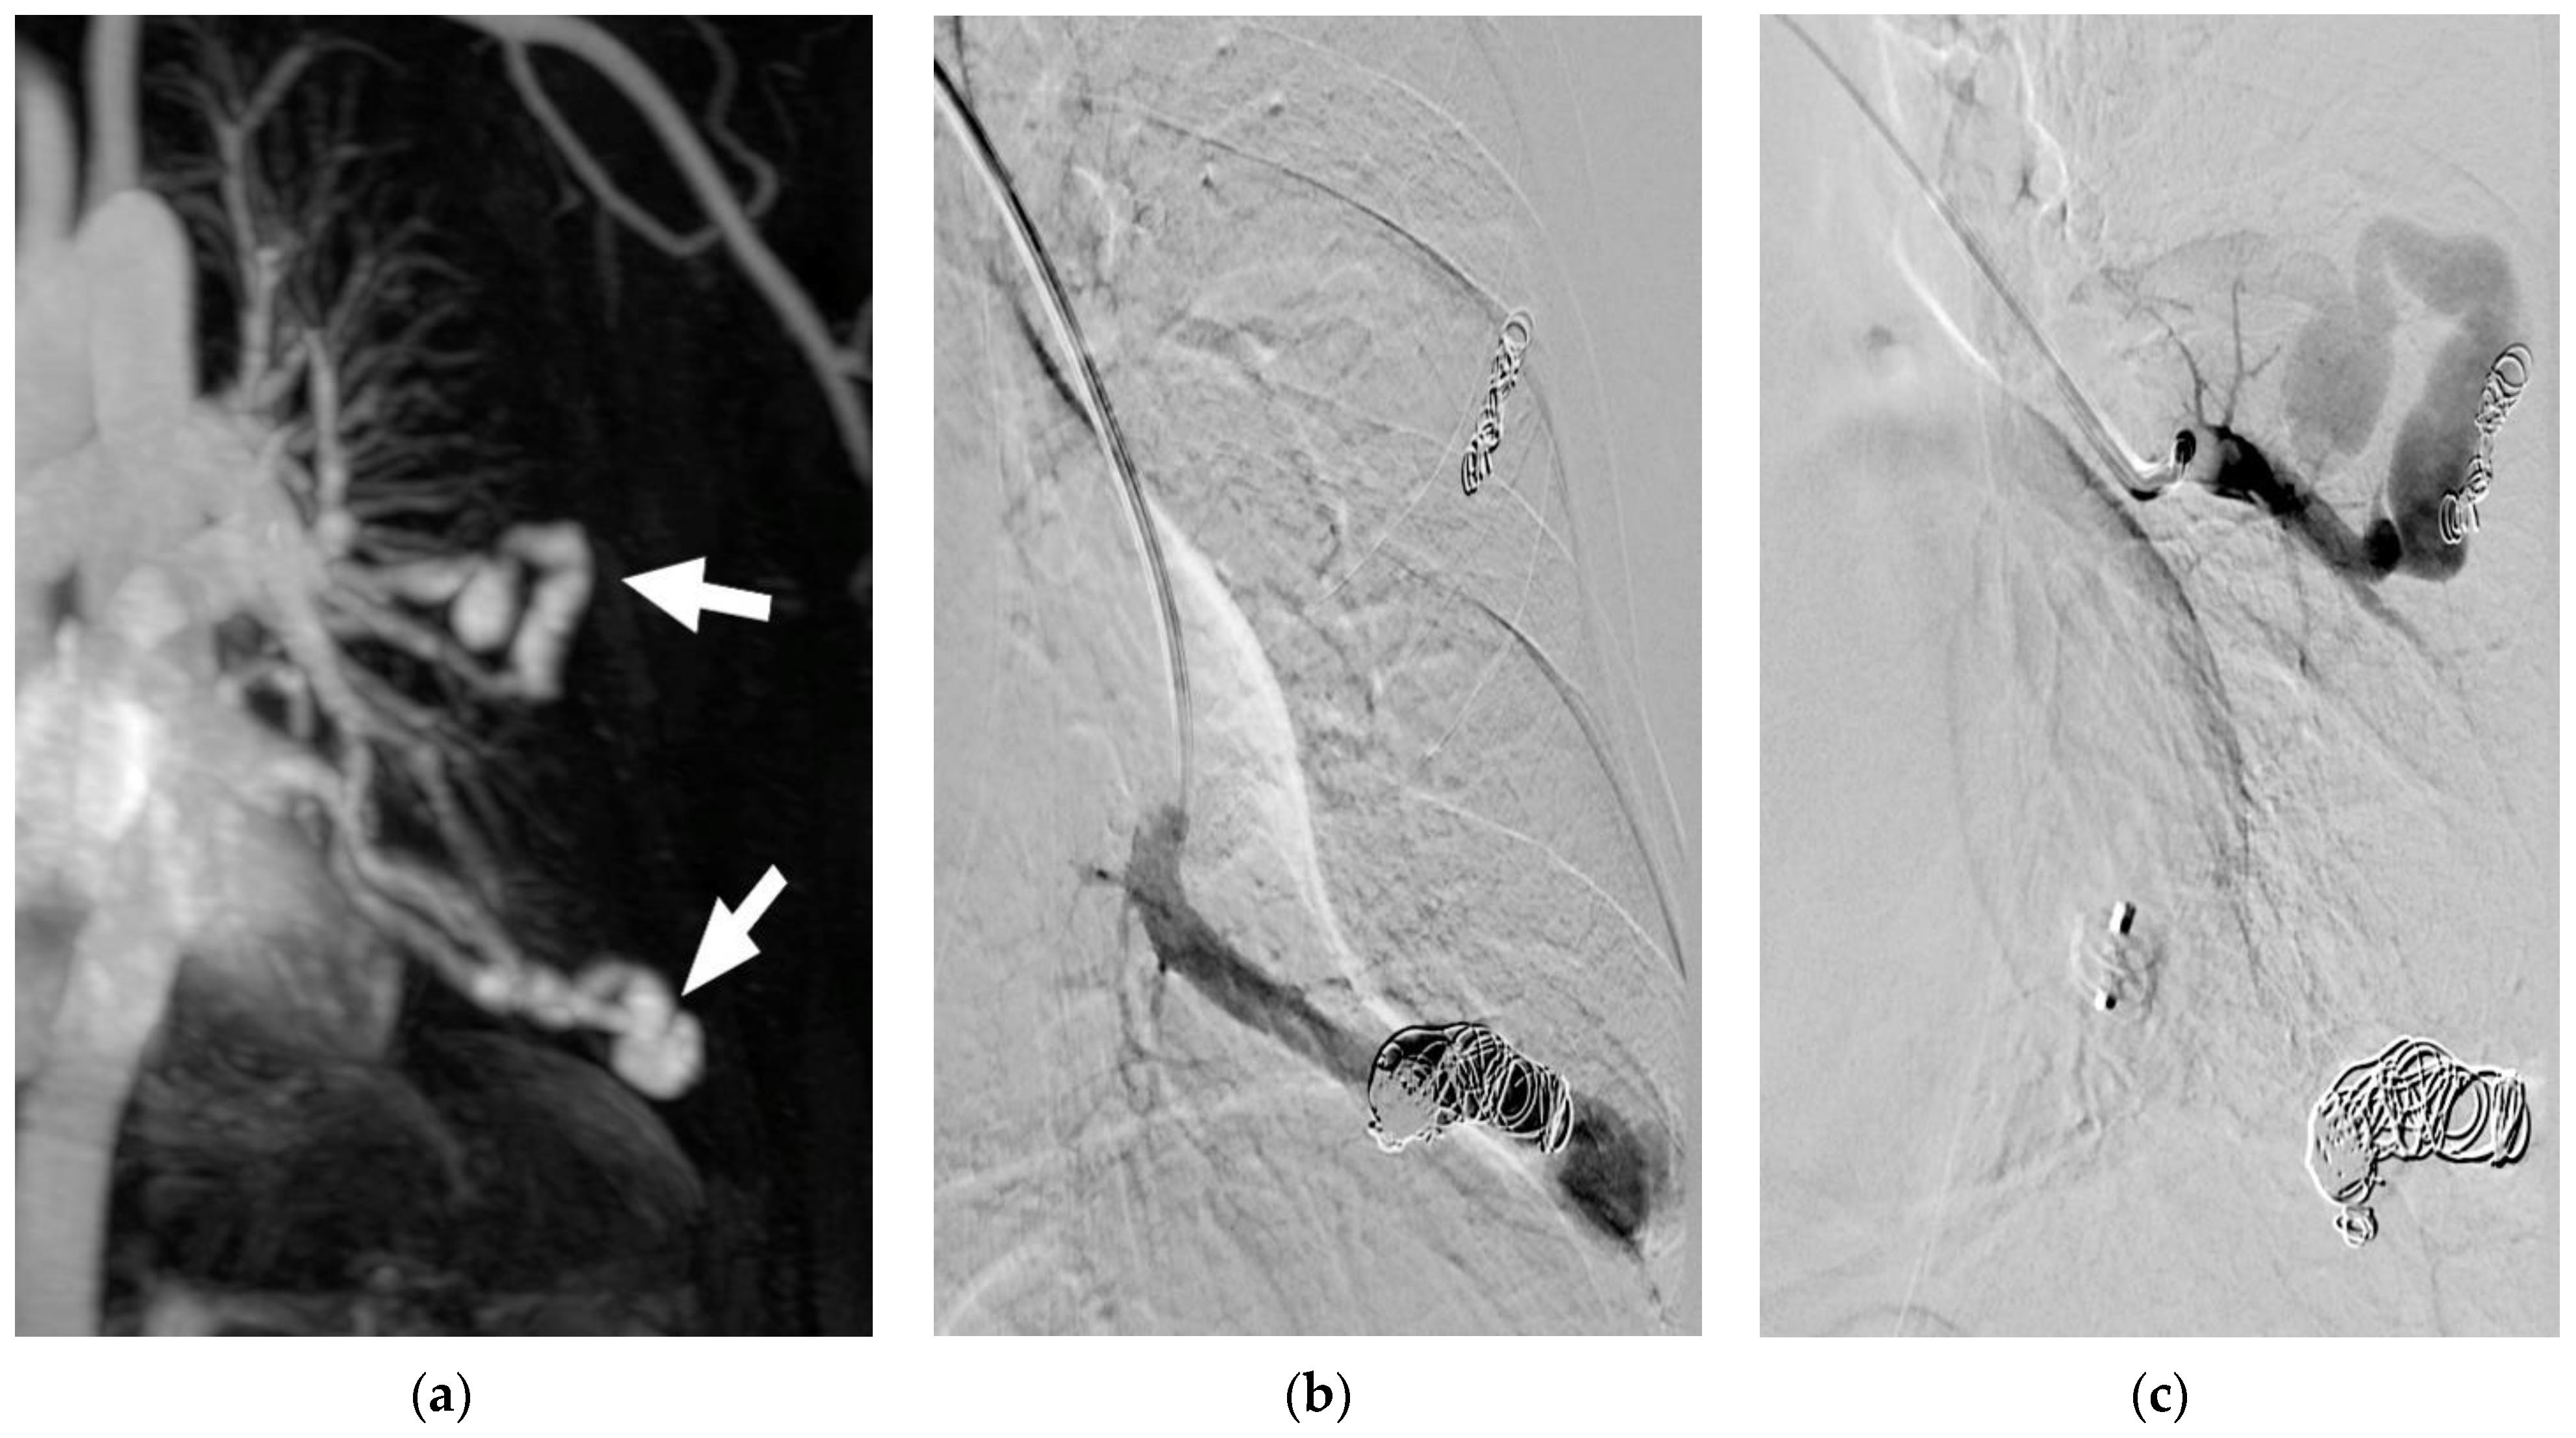

Figure 1. Cerebral DWI (b = 800) demonstrating subacute cerebral ischemia, in this case prior to embolization of multiple PAVMs. The newly developed lesion arose between screening for PAVM and the day of interventional therapy, but the patient did not exhibit any clinical signs or symptoms. This example highlights the importance of DWI for the detection of pre-existing cerebral ischemia, as well as peri-interventional cerebral insult.